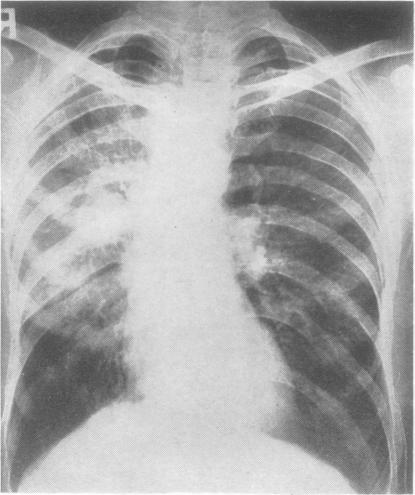

Thoracic actinomycosis.

Thorax. 1957 Jun;12(2):99-124. doi: 10.1136/thx.12.2.99.